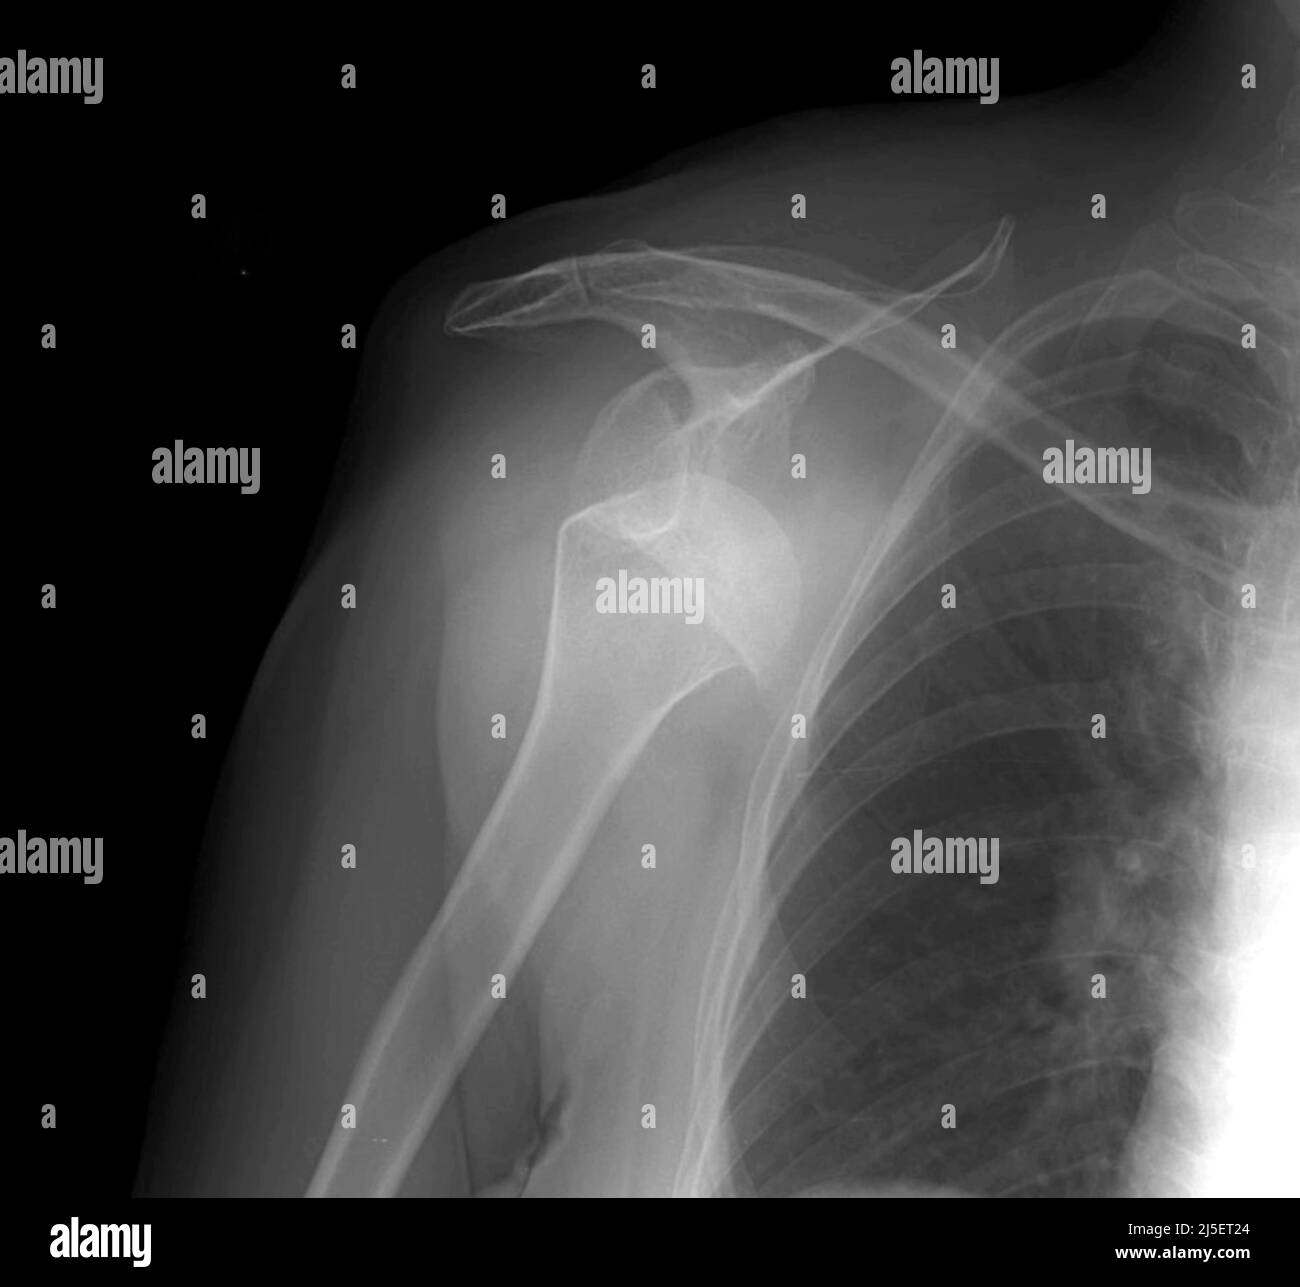

How To Identify Shoulder Dislocation X Ray . The humeral head is subcoracoid in. The condition is also called luxatio erecta because the arm appears to be permanently held upward,. Capturing images from different angles. Anteroposterior radiograph shows luxatio erecta, or inferior dislocation of the shoulder. For any suspected dislocation, obtain 3 views: The glenohumeral joint will be widened and the. The humeral head should be on the glenoid in any other view. The arm is abducted, elevated, and fixed. If the humeral head lies under the coracoid process, think anterior. An inferior shoulder dislocation is the least common form of shoulder dislocation.

Anterior Shoulder Dislocation, PreReduction AP XRay, Annotated. JETem How To Identify Shoulder Dislocation X Ray The arm is abducted, elevated, and fixed. For any suspected dislocation, obtain 3 views: Capturing images from different angles. Anteroposterior radiograph shows luxatio erecta, or inferior dislocation of the shoulder. The humeral head should be on the glenoid in any other view. An inferior shoulder dislocation is the least common form of shoulder dislocation. The humeral head is subcoracoid in.. How To Identify Shoulder Dislocation X Ray.

AP Xray of the shoulder illustrating anterior shoulder dislocation How To Identify Shoulder Dislocation X Ray The humeral head should be on the glenoid in any other view. The condition is also called luxatio erecta because the arm appears to be permanently held upward,. The humeral head is subcoracoid in. The glenohumeral joint will be widened and the. If the humeral head lies under the coracoid process, think anterior. For any suspected dislocation, obtain 3 views:. How To Identify Shoulder Dislocation X Ray.

Anteriorposterior Xray showing the anteriorly dislocated right How To Identify Shoulder Dislocation X Ray An inferior shoulder dislocation is the least common form of shoulder dislocation. If the humeral head lies under the coracoid process, think anterior. Anteroposterior radiograph shows luxatio erecta, or inferior dislocation of the shoulder. For any suspected dislocation, obtain 3 views: The humeral head should be on the glenoid in any other view. The arm is abducted, elevated, and fixed.. How To Identify Shoulder Dislocation X Ray.

Anterior Shoulder Dislocation, Post Reduction AP XRay, Annotated. JETem How To Identify Shoulder Dislocation X Ray The humeral head should be on the glenoid in any other view. Anteroposterior radiograph shows luxatio erecta, or inferior dislocation of the shoulder. The arm is abducted, elevated, and fixed. The condition is also called luxatio erecta because the arm appears to be permanently held upward,. An inferior shoulder dislocation is the least common form of shoulder dislocation. If the. How To Identify Shoulder Dislocation X Ray.